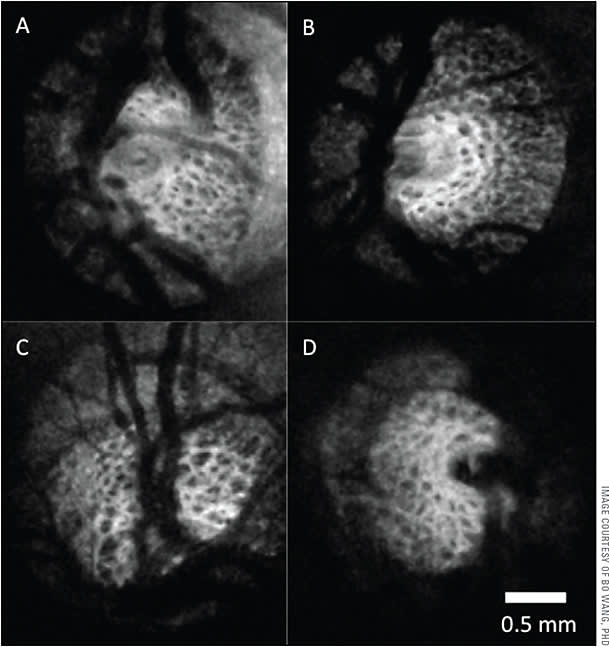

Finally, unlike the narrow imaging depth of focus with SD-OCT, SS-OCT can image a large axial window, capturing vitreous and retina simultaneously, while imaging as deep as the choroid and lamina cribrosa (LC). A wide-field imaging protocol also provides the capability of scanning the optic nerve and macula simultaneously. These unique features of SS-OCT facilitate broad clinical applications for imaging the anterior and posterior segment in glaucoma patients.

The longer wavelength of SS-OCT allows for improved visualization of deeper ocular structures in the glaucomatous eye, specifically the choroid and LC.7 Choroidal thickness has been implicated to have a role in the glaucomatous disease process. Choroidal thickness in highly myopic eyes with normal-tension glaucoma is significantly thinner than in myopic eyes without glaucoma.8 Although the precise pathogenesis of glaucoma remains unknown, the LC is the presumed site of axonal injury in glaucoma. SS-OCT imaging of LC allows for identification of focal defects and changes in the overall microarchitecture (thinner LC and LC displacement) that are associated with rapid glaucomatous progression.9,10